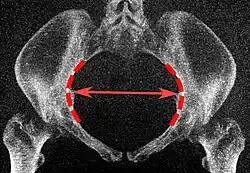

The diameters or conjugates of the pelvis are measured at the pelvic inlet and outlet and as oblique diameters.

| Name | Description | Average measurement in female |

|---|---|---|

| Anteroposterior or conjugate diameter or conjugata vera | Extends from the upper margin of the pubic symphysis to the sacrococcygeal joint; | about 110 mm. |

| Transverse diameter | Extends across the greatest width of the superior aperture, from the middle of the brim on one side to the same point on the opposite; | about 135 mm. |

| Oblique diameter | Extends from the iliopectineal eminence of one side to the sacroiliac articulation of the opposite side; | about 125 mm. |

| Anatomical conjugate | Extends from the pubic symphysis to the promontory; | about 120 mm. |

| Diagonal conjugate | Extends from lower margin of the pubic symphysis to the sacral promontory; | about 130 mm. |

| Straight conjugate | Extends from the lower border of the pubic symphysis to the tip of coccyx. The coccyx can bend posteriorly and expand the diameter with 25 mm; | about 95 mm (+ 25 mm). |

| Median conjugate | Extends from the lower border of the pubic symphysis to the lower border of the sacrum; | about 115 mm. |

Low-dose CT scan of the transverse diameter of the pelvic inlet, as part of pelvimetry